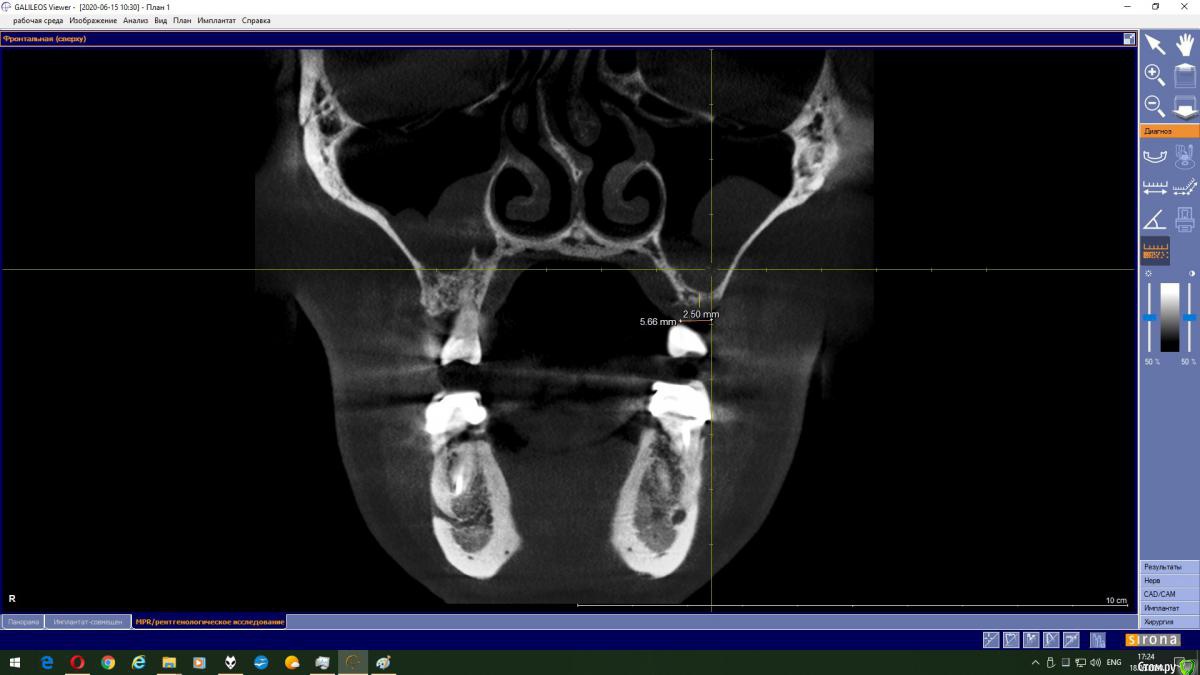

Magnoliya Опубликовано 18 июня, 2020 Поделиться Опубликовано 18 июня, 2020 Здравствуйте, прошу Вашей помощи и консультации. Все доктора, у которых я уже побывала говорят противоположные вещи, сложно принять решение. Очень надеюсь, что вы сможете посмотреть КТ, и выскажете своё мнение. http://fayloobmennik.cloud/7398744 Предыстория удалила 6 и 7 на левой верхней челюсти в надежде, что через 4 месяца сделаю открытый синус-лифтинг с подсадкой костной ткани и затем установлю импланты,но когда принесла КТ врачу перед операцией, он сказал, что синус лифтинг противопоказан, так как в гайморовой пазухе киста, и костной ткани мало, от слова ОЧЕНЬ МАЛО. В его видении решении моей проблемы был скуловой имплант Zigoma. при котором сразу после операции я выйду с зубами, естественно с другой суммой на операцию, на которую я не расчитывала. Тут я решила пойти на консультацию к другим специалистам, чтоб принять решение. На сегодняшний день есть 3 варианта, которые озвучили мне доктора: 1. Операция со скуловым имплантом с одномоментной установкой коронок2. Обратиться к ЛОРу и удалить кисту, затем синус лифтинг и т.д.3. Один врач сказал мне, что киста не мешает и можно делать синус лифтинг не удаляя кисту??? Действительно ли так? Можно ли избежать операции по удалению кисты? Заранее спасибо всем тем, кто хоть как то поможет советом Ссылка на комментарий

колесников Опубликовано 18 июня, 2020 Поделиться Опубликовано 18 июня, 2020 Глупости какие! Для чего зигомы? Доктора видимо смутил рельеф дна пазухи,там много перегородок,выступов,что затрудняет отслаивание мембраны. Можно провести имплантацию одновременно с синуслмфтингом,а кисту и вовсе не трогать. 1 Ссылка на комментарий

Bier Опубликовано 18 июня, 2020 Поделиться Опубликовано 18 июня, 2020 Данную кисту убирать не нужно. Нет показаний для зигомы. Делайте синуслифтинг и имплантат. Ссылка на комментарий

колесников Опубликовано 19 июня, 2020 Поделиться Опубликовано 19 июня, 2020 Выходить можно сделать синус лифтинг не трогая кисту. В дальнейшем ничем это не грозит? Я имею ввиду киста не вытечет на импланты? И может ли киста со временем рассосаться сама? это не инфекционного происхождения киста,слизистая железка закупорилась,может надуваться,может лопнуть самостоятельно,у вас она на боковой стенке пазухи,синуслмфтингу не помеха Ссылка на комментарий